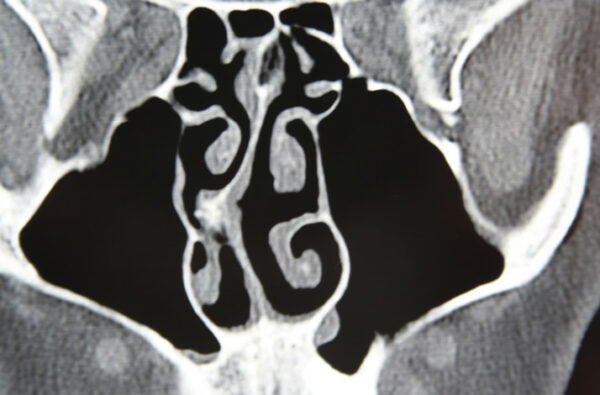

The shape of your nasal cavity could be the cause of chronic sinusitis. The nasal septum is the wall dividing the nasal cavity into halves; it is composed of a central supporting skeleton covered on each side by mucous membrane. The front portion of this natural partition is a firm but bendable structure made mostly of cartilage and is covered by skin that has a substantial supply of blood vessels. The ideal nasal septum is exactly midline, separating the left and right sides of the nose into passageways of equal size.

A deviated septum occurs when the septum is severely shifted away from the midline. The most common symptom from a badly deviated or crooked septum is difficulty breathing through the nose. The symptoms are usually worse on one side, and sometimes actually occur on the side opposite the bend. In some cases the crooked septum can interfere with the drainage of the sinuses, resulting in repeated sinus infections.

Septal deviation occurs when the nasal septum, the thin wall between the nostrils, is crooked or off-center, causing breathing difficulties and other symptoms. It can be present at birth or result from injury.

An ENT specialist can diagnose a deviated septum through a physical examination and nasal endoscopy, which provides a clear view of the nasal passages and any abnormalities.